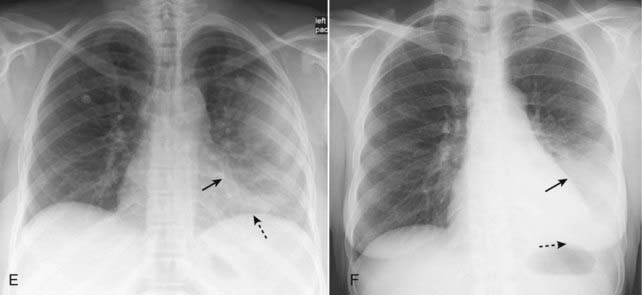

image

Figure 7-13 Resolving pneumonia.

Pneumonia, especially pneumococcal pneumonia, can resolve in 2-3 days if the organism is sensitive to the antibiotic administered. Most pneumonias, like that in the lingula in radiographs taken four days apart shown in (A) and (B), typically resolve from within (vacuolize), gradually disappearing in a patchy fashion over days or weeks. If a pneumonia does not resolve in weeks, you should consider the presence of an underlying obstructing lesion, such as a neoplasm, that is preventing adequate drainage from that portion of the lung.